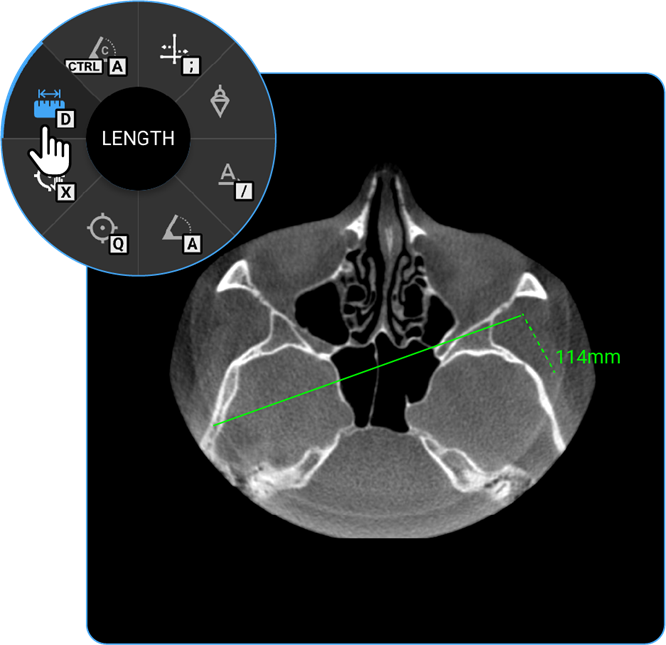

How Do I Measure Length?

• Usage: Measure distance between two points.

• Hotkey: Press D.

• Clinical Utility: Helps measure anatomical structures or lesion sizes.

• Locate the Length tool on the wheel and click on it to calculate the distance between two points on the image, useful for measuring anatomical structures.

1. Length: Locate the Length tool on the wheel and click on it to calculate the distance between two points on the image, useful for measuring anatomical structures.